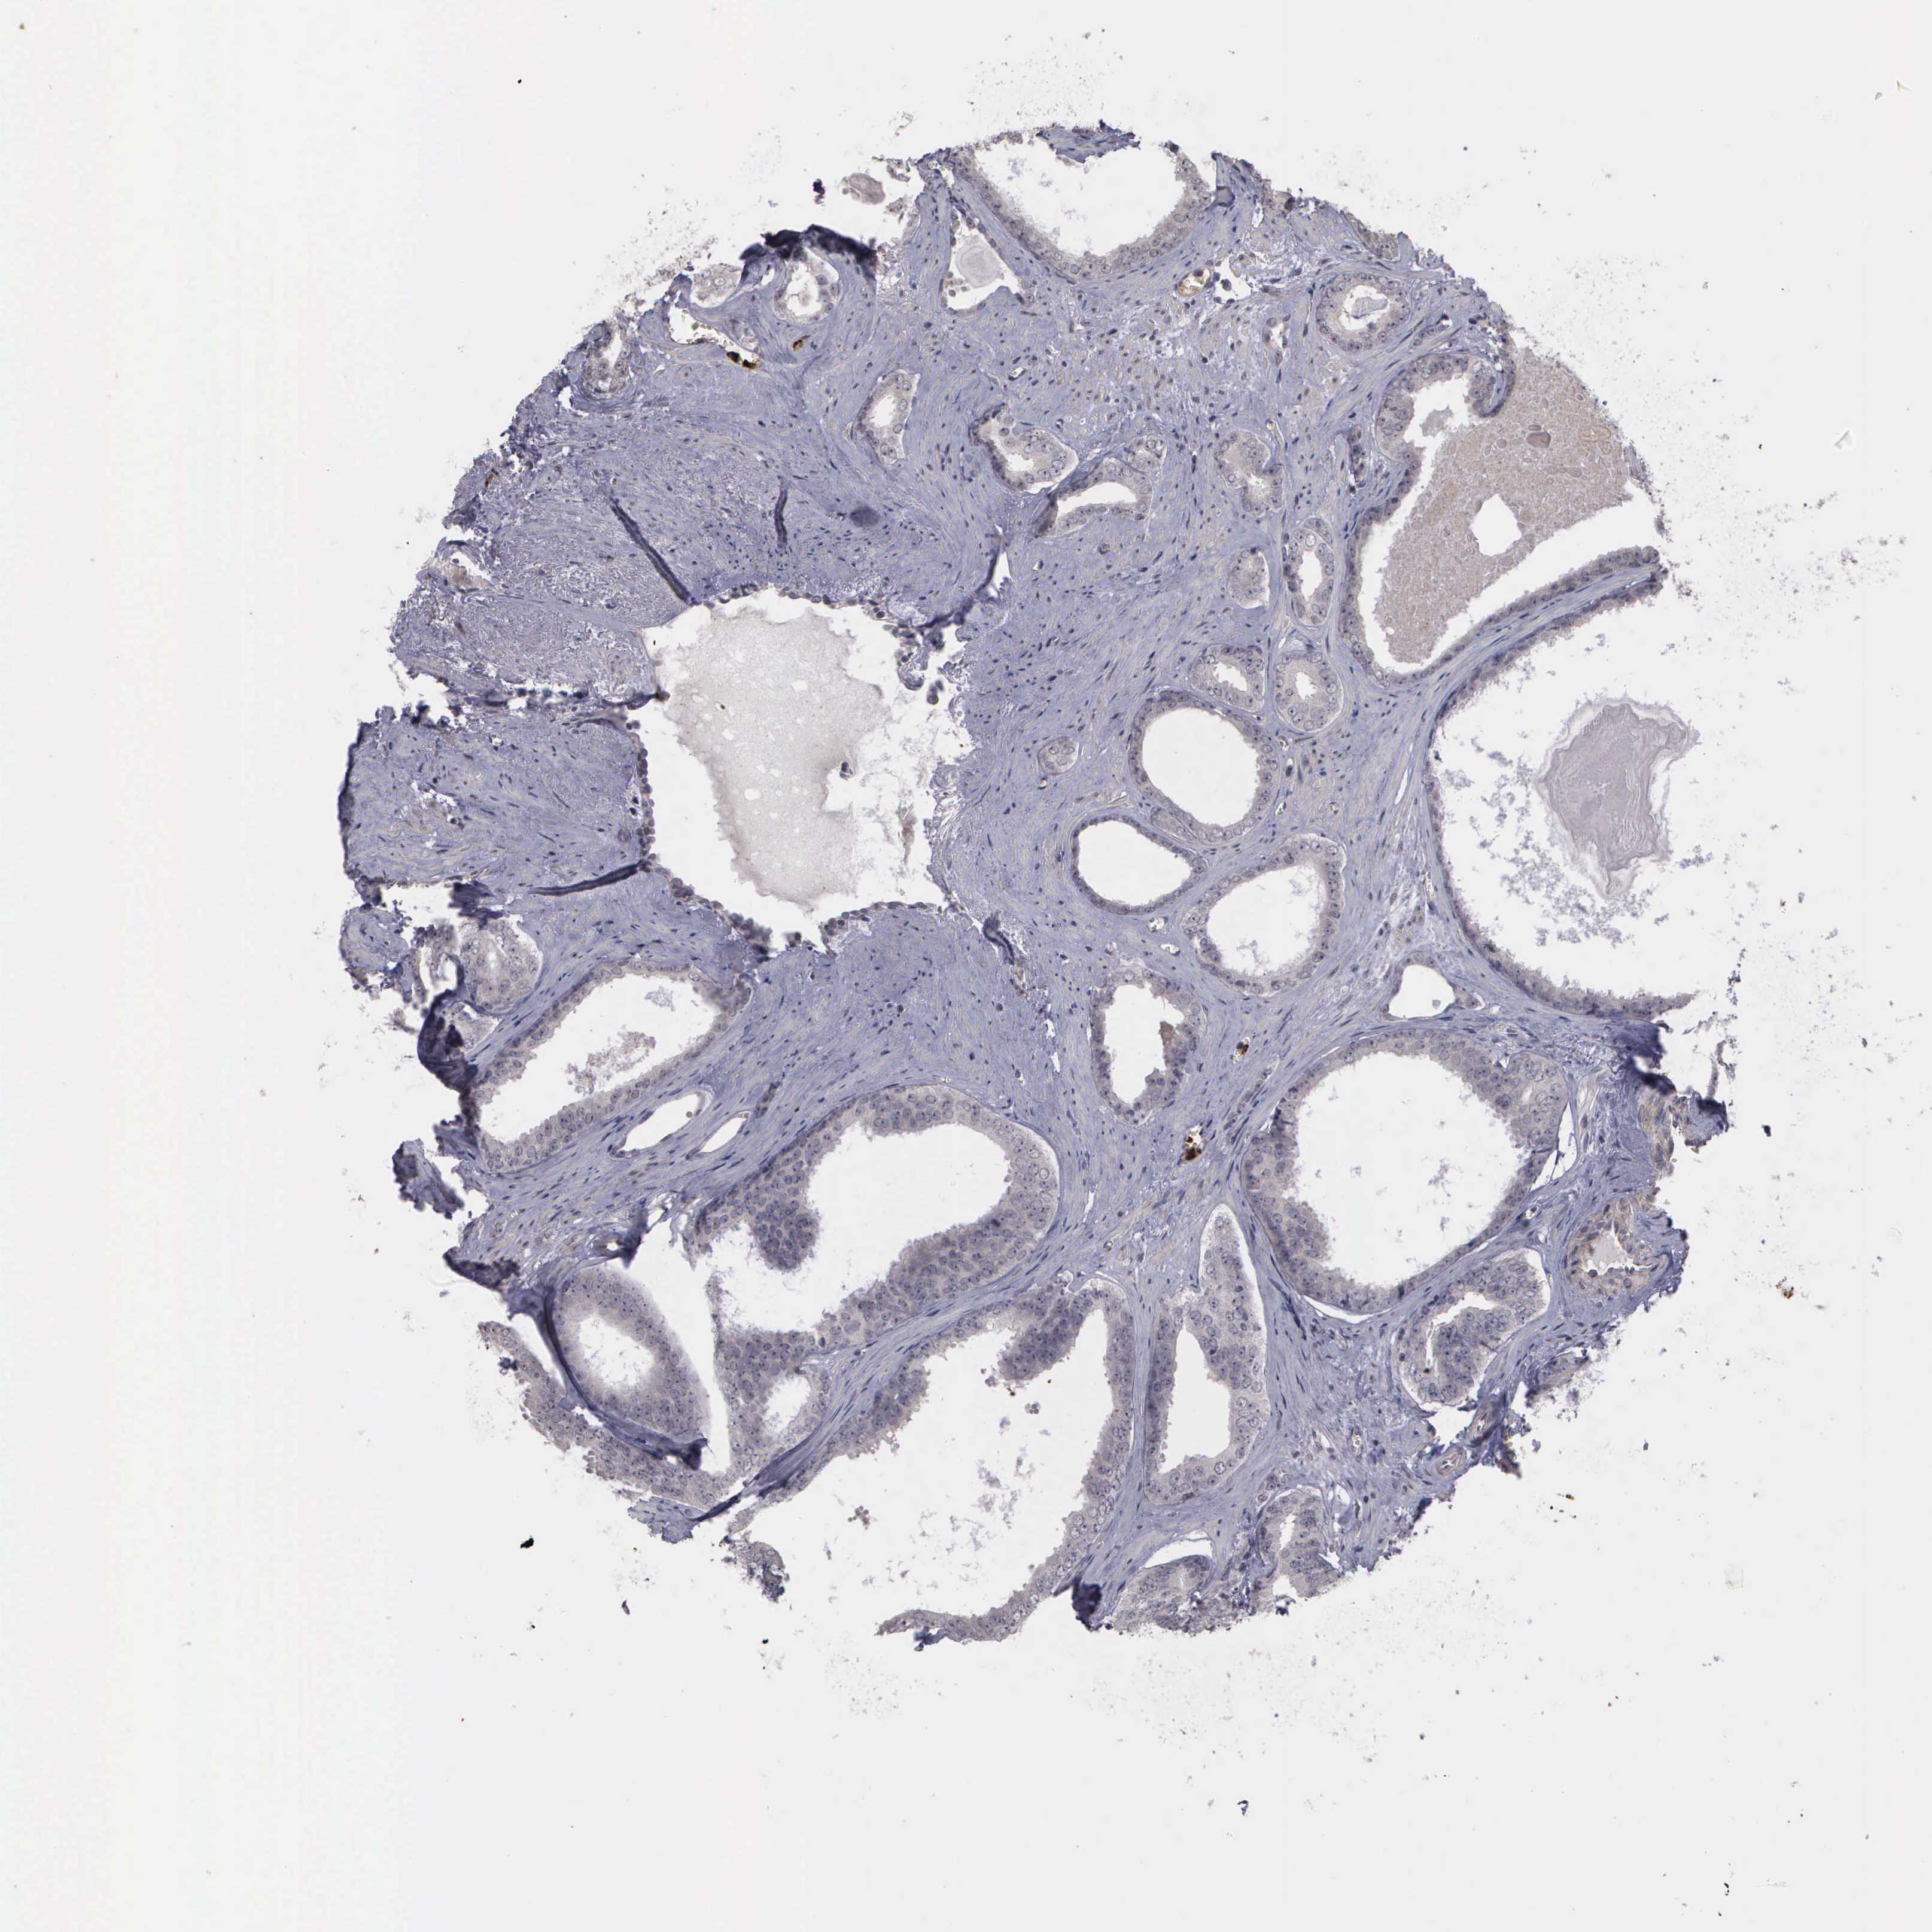

PROSTATE CANCER - Protein expressioni

A mouse-over function shows sample information and annotation data. Click on an image to view it in a full screen mode. Samples can be filtered based on level of antibody staining by selecting one or several of the following categories: high, medium, low and not detected. The assay and annotation is described here.

Note that samples used for immunohistochemistry by the Human Protein Atlas do not correspond to samples in the TCGA dataset.

Antibody stainingi

Antibody staining in the annotated cell types in the current human tissue is reported as not detected, low, medium, or high, based on conventional immunohistochemistry profiling in selected tissues. This score is based on the combination of the staining intensity and fraction of stained cells.

Each image is clickable and will lead to virtual microscopy that enables deeper exploration of all samples and also displays staining intensity scores, fraction scores and subcellular localization as well as patient and tissue information for each sample.

Adenocarcinoma, High grade

Adenocarcinoma, NOS

Adenocarcinoma, Low grade

Adenocarcinoma, Medium grade